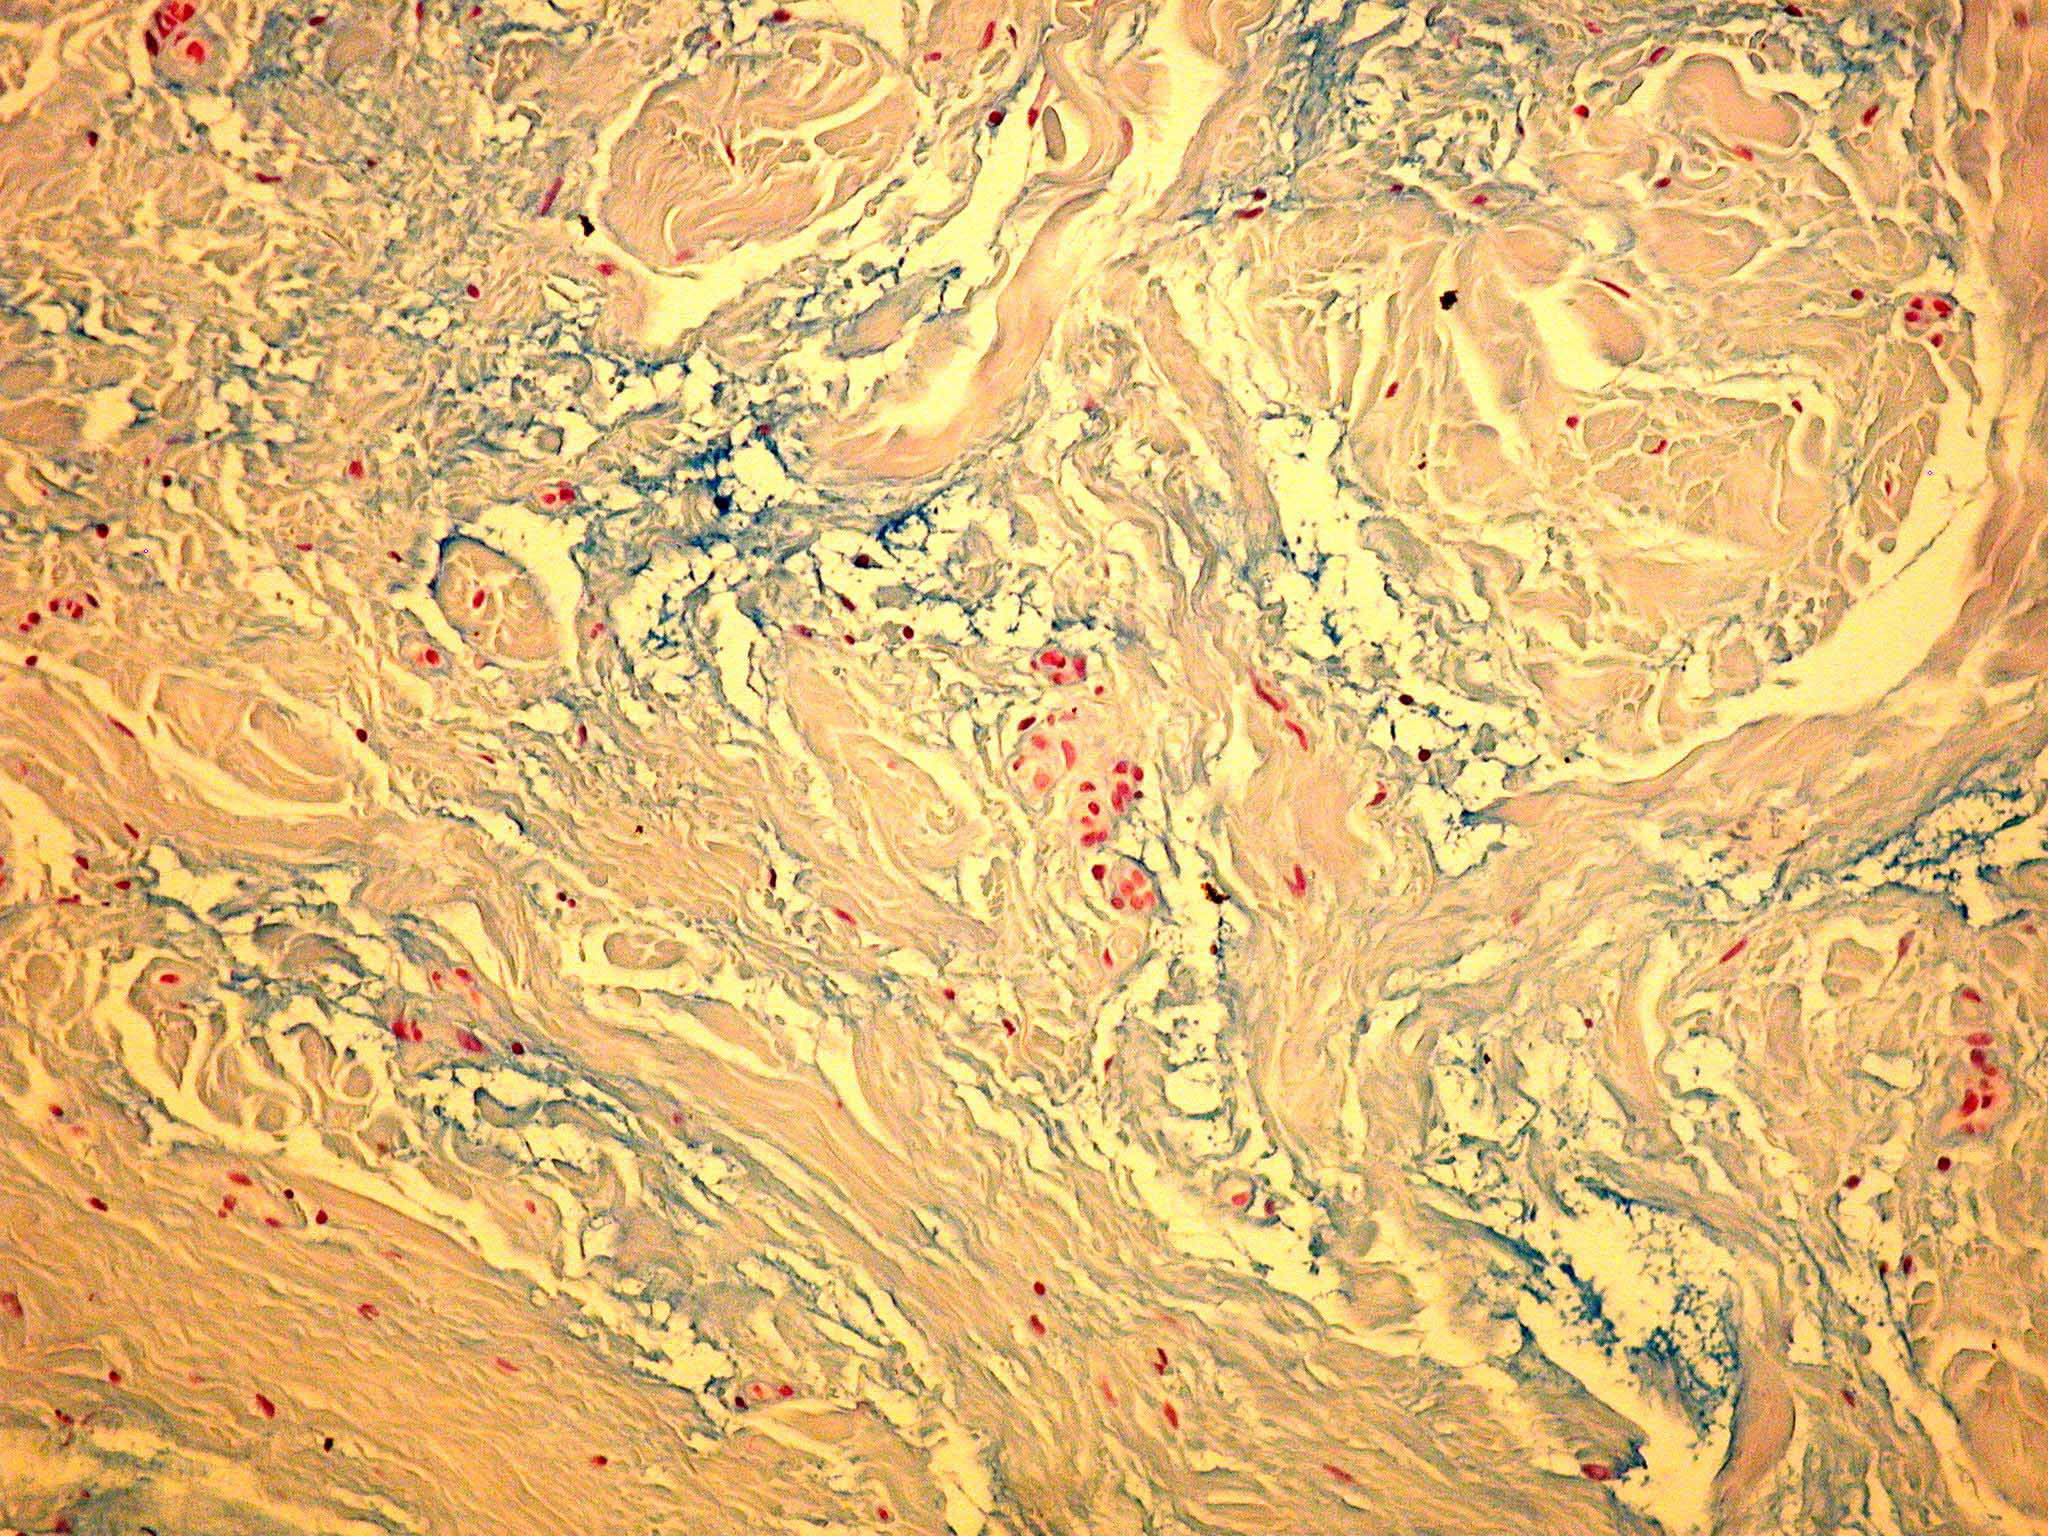

Myxoedema =الوذمة المخاطية